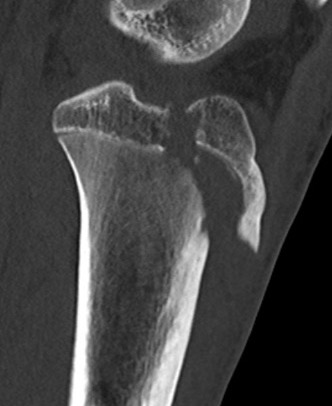

CT / MRI scan

CT scan - ensure fracture doesn't involve the physis / disrupt articular surface

Type IIB